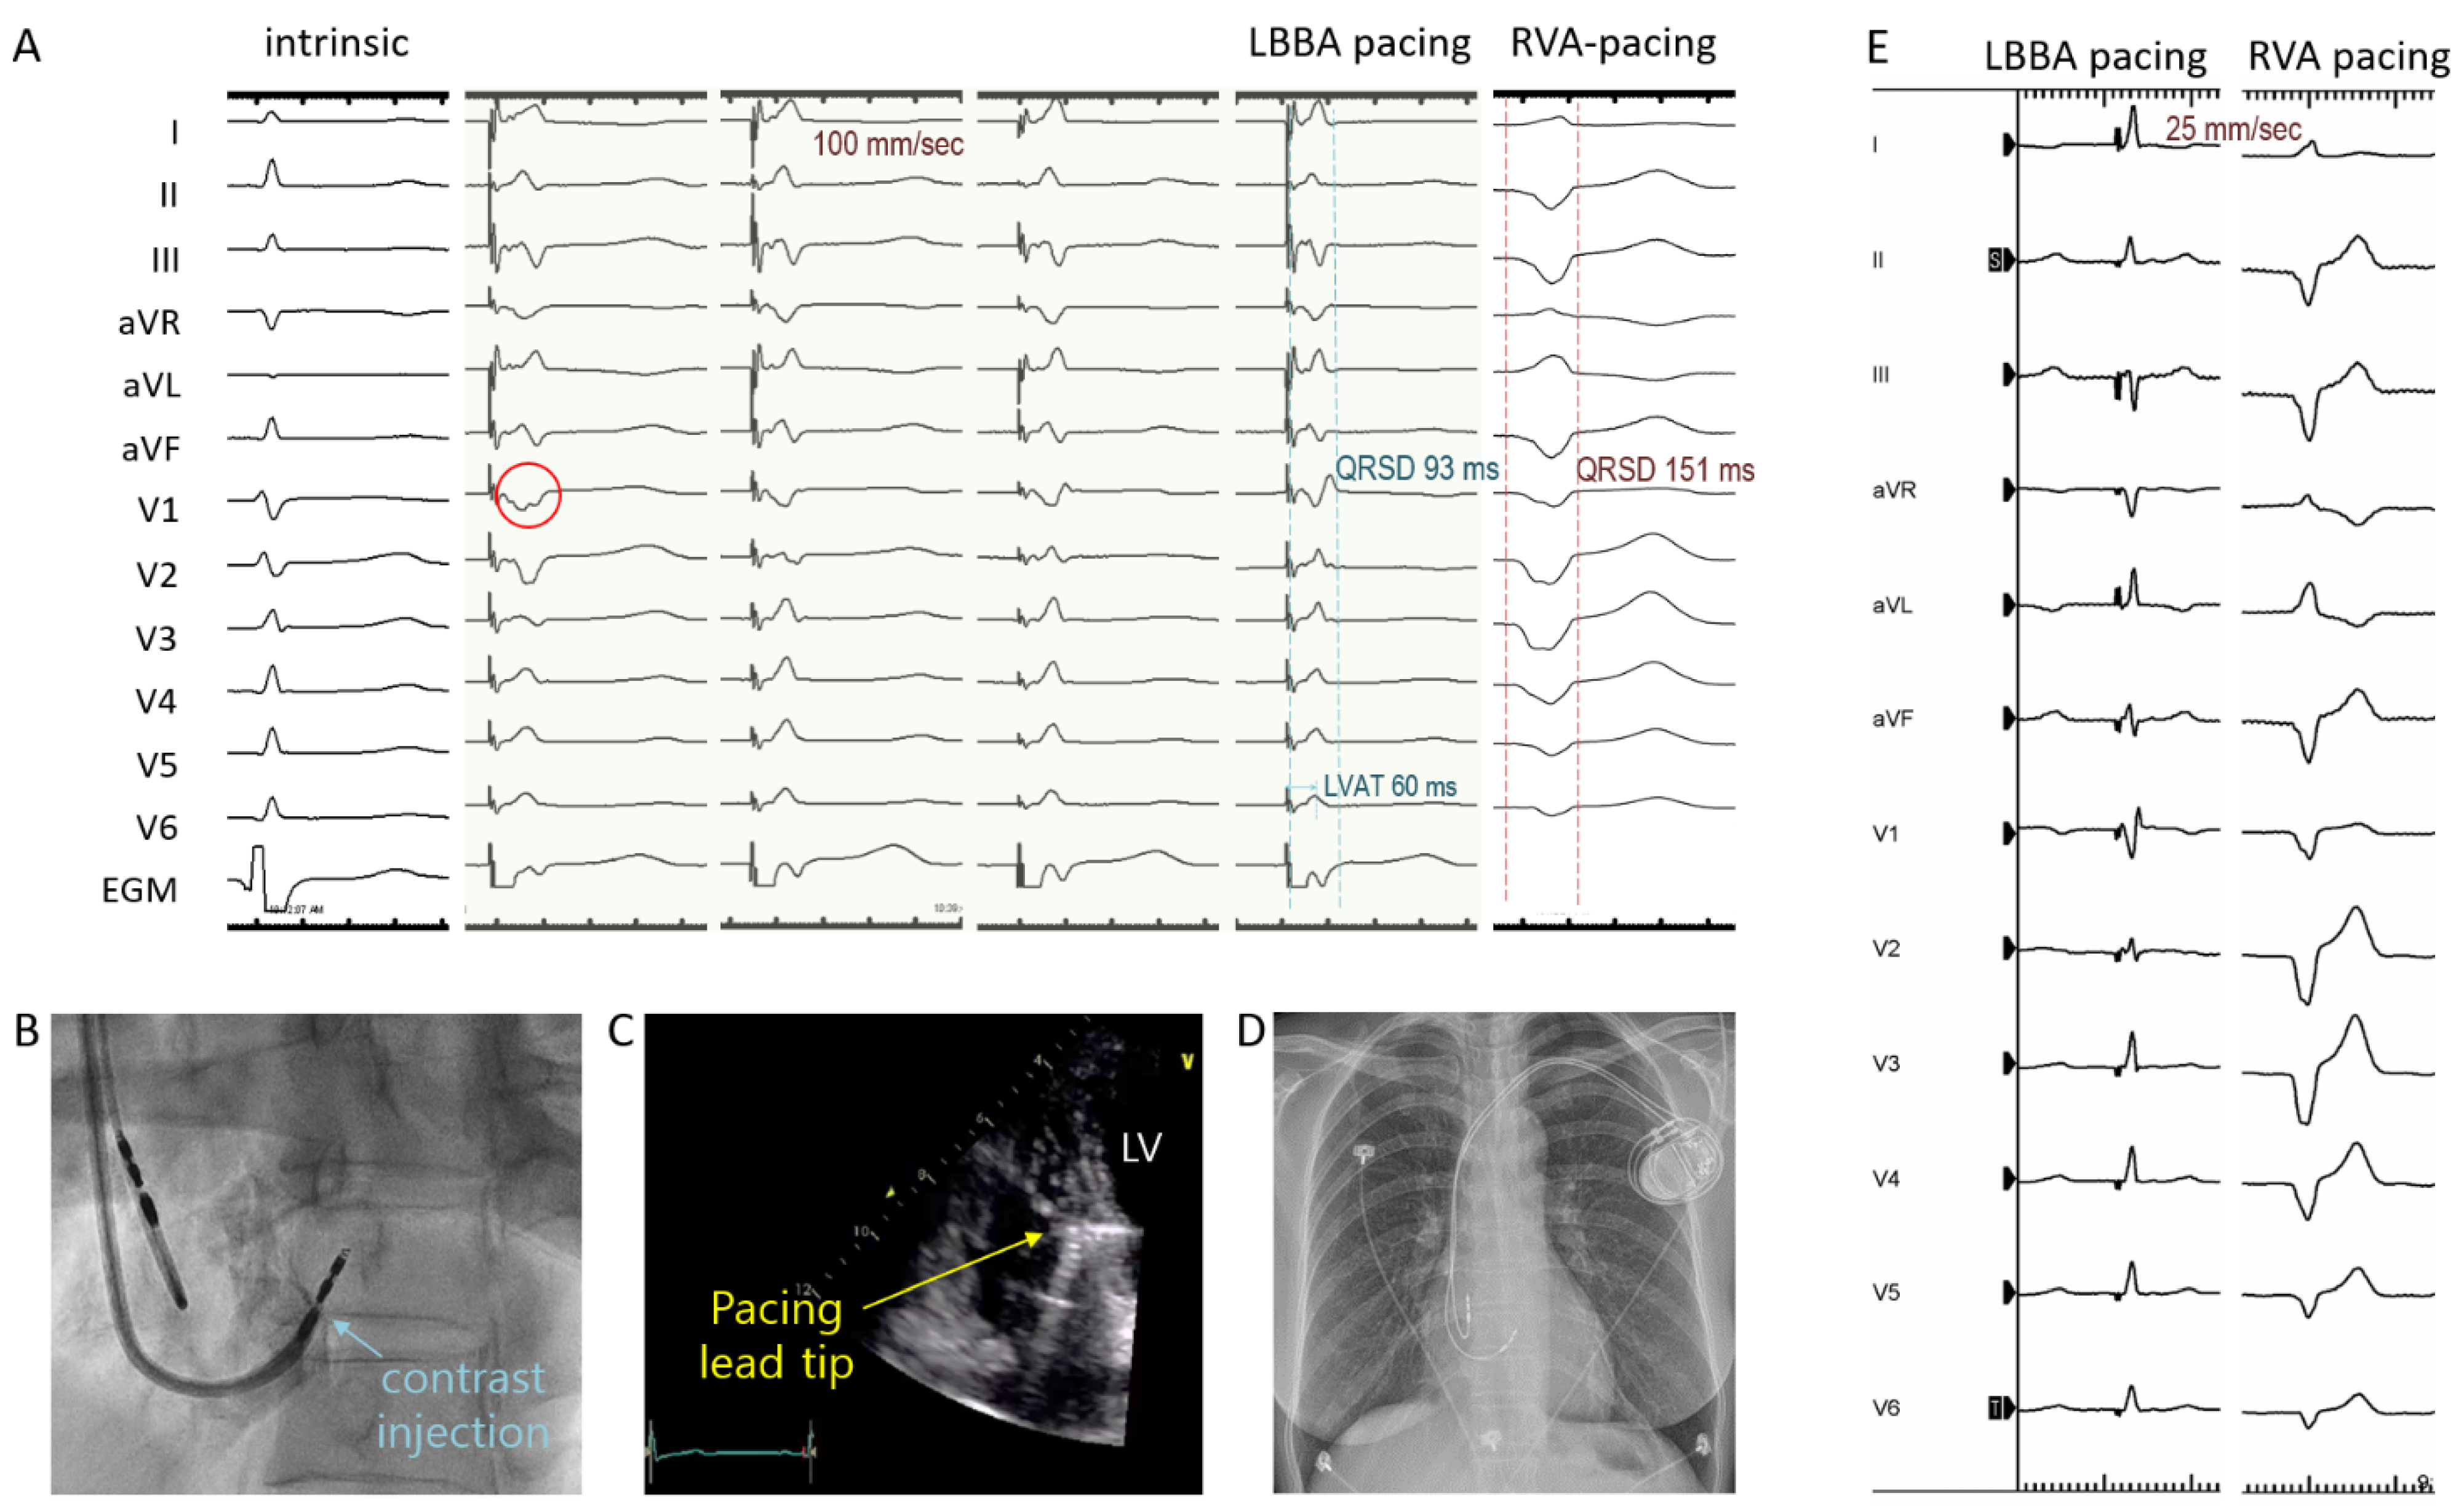

4.2. Efficacy and Safety of LBBAp Using SDES Leads and New Fixed Curve Delivery Sheath

4.3. Efficacy of Physiological Pacing Using the New Implant Approach